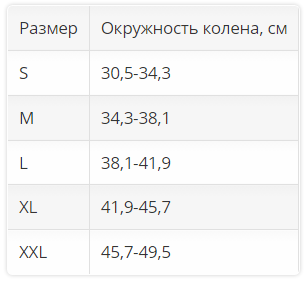

Размер. Для определения размера нужно измерить окружность колена.

| Размер | Окружность колена, см |

| S | 30,5-34,3 |

| M | 34,3-38,1 |

| L | 38,1-41,9 |

| XL | 41,9-45,7 |

| XXL |

45,7-49,5 |